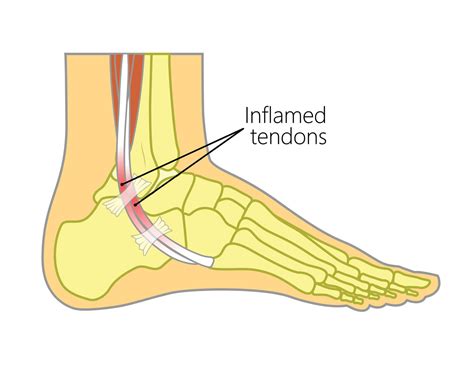

To grasp the significance of a Peroneus Longus Tendon Tear, it is helpful to understand the function of the peroneal tendons. There are two primary peroneal tendons—the peroneus longus and the peroneus brevis. They run side-by-side along the lateral (outer) aspect of the ankle. Their primary roles include:

When these tendons are subjected to excessive stress, repetitive motion, or sudden trauma, they can develop tears, tendonitis, or even complete ruptures. Damage to the peroneus longus is often associated with chronic ankle instability.